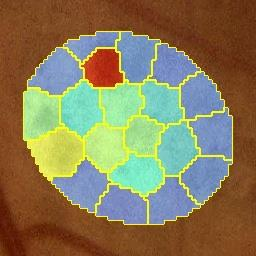

Deep-learning-based approaches for retinal lesion segmentation often require an abundant amount of precise pixel-wise annotated data. However, coarse annotations such as circles or ellipses for outlining the lesion area can be six times more efficient than pixel-level annotation. Therefore, this paper proposes an annotation refinement network to convert a coarse annotation into a pixel-level segmentation mask. Our main novelty is the application of the prototype learning paradigm to enhance the generalization ability across different datasets or types of lesions. We also introduce a prototype weighing module to handle challenging cases where the lesion is overly small. The proposed method was trained on the publicly available IDRiD dataset and then generalized to the public DDR and our real-world private datasets. Experiments show that our approach substantially improved the initial coarse mask and outperformed the non-prototypical baseline by a large margin. Moreover, we demonstrate the usefulness of the prototype weighing module in both cross-dataset and cross-class settings.

翻译:对视网膜损伤分解的深学习方法往往需要大量精确的像素说明数据。然而,圆形或椭圆等粗略说明概述损害区比像素级注解效率高六倍于像素级注解。因此,本文件建议建立一个批注性改进网络,将粗略注解转换成像素级分解面罩。我们的主要新颖之处是应用原型学习模式,提高不同数据集或不同类型损伤的概括性能力。我们还引入一个原型称模块,在病变过小的情况下处理具有挑战性的个案。拟议方法在公开提供的IDRID数据集上进行了培训,然后推广到公众解甲返乡和我们真实世界的私人数据集。实验表明,我们的方法大大改进了最初的粗口罩,大大超越了非protodic基线。此外,我们还展示了原型称称称模块在交叉数据集和跨类环境中的效用。